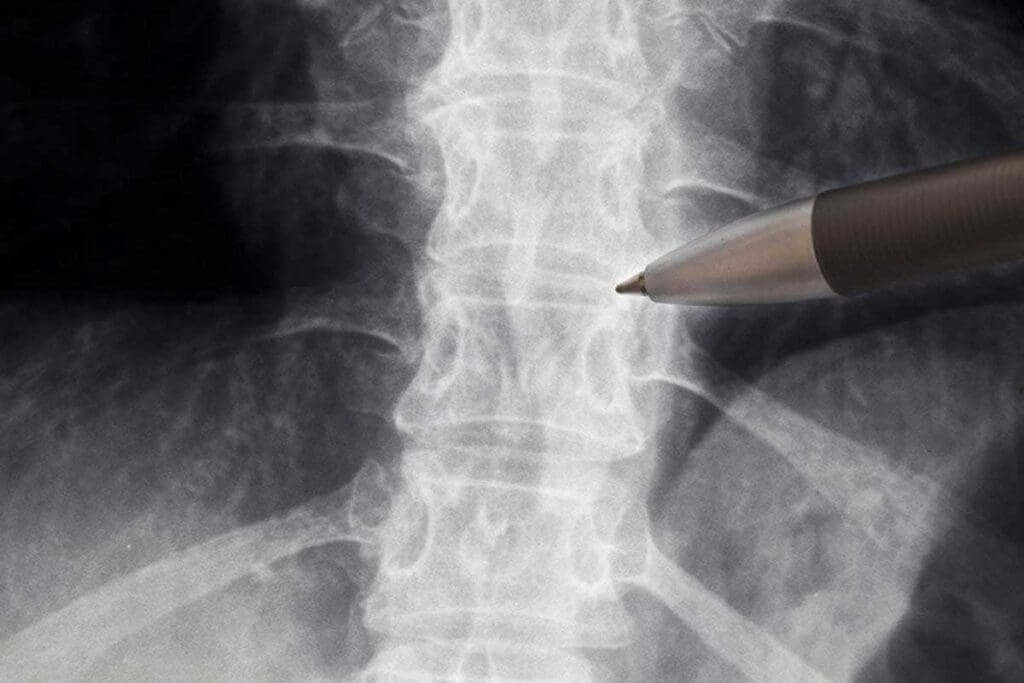

Spinal and Pelvic Fractures

Spinal and pelvic fractures are tough to diagnose because of their complex anatomy. MRI gives a full view of these areas, including bones, discs, and soft tissues. This is key for seeing how bad the injury is and if there are nerve problems or instability.

For example, MRI can tell if a spinal fracture is new or old. Knowing this helps doctors plan the right treatment.